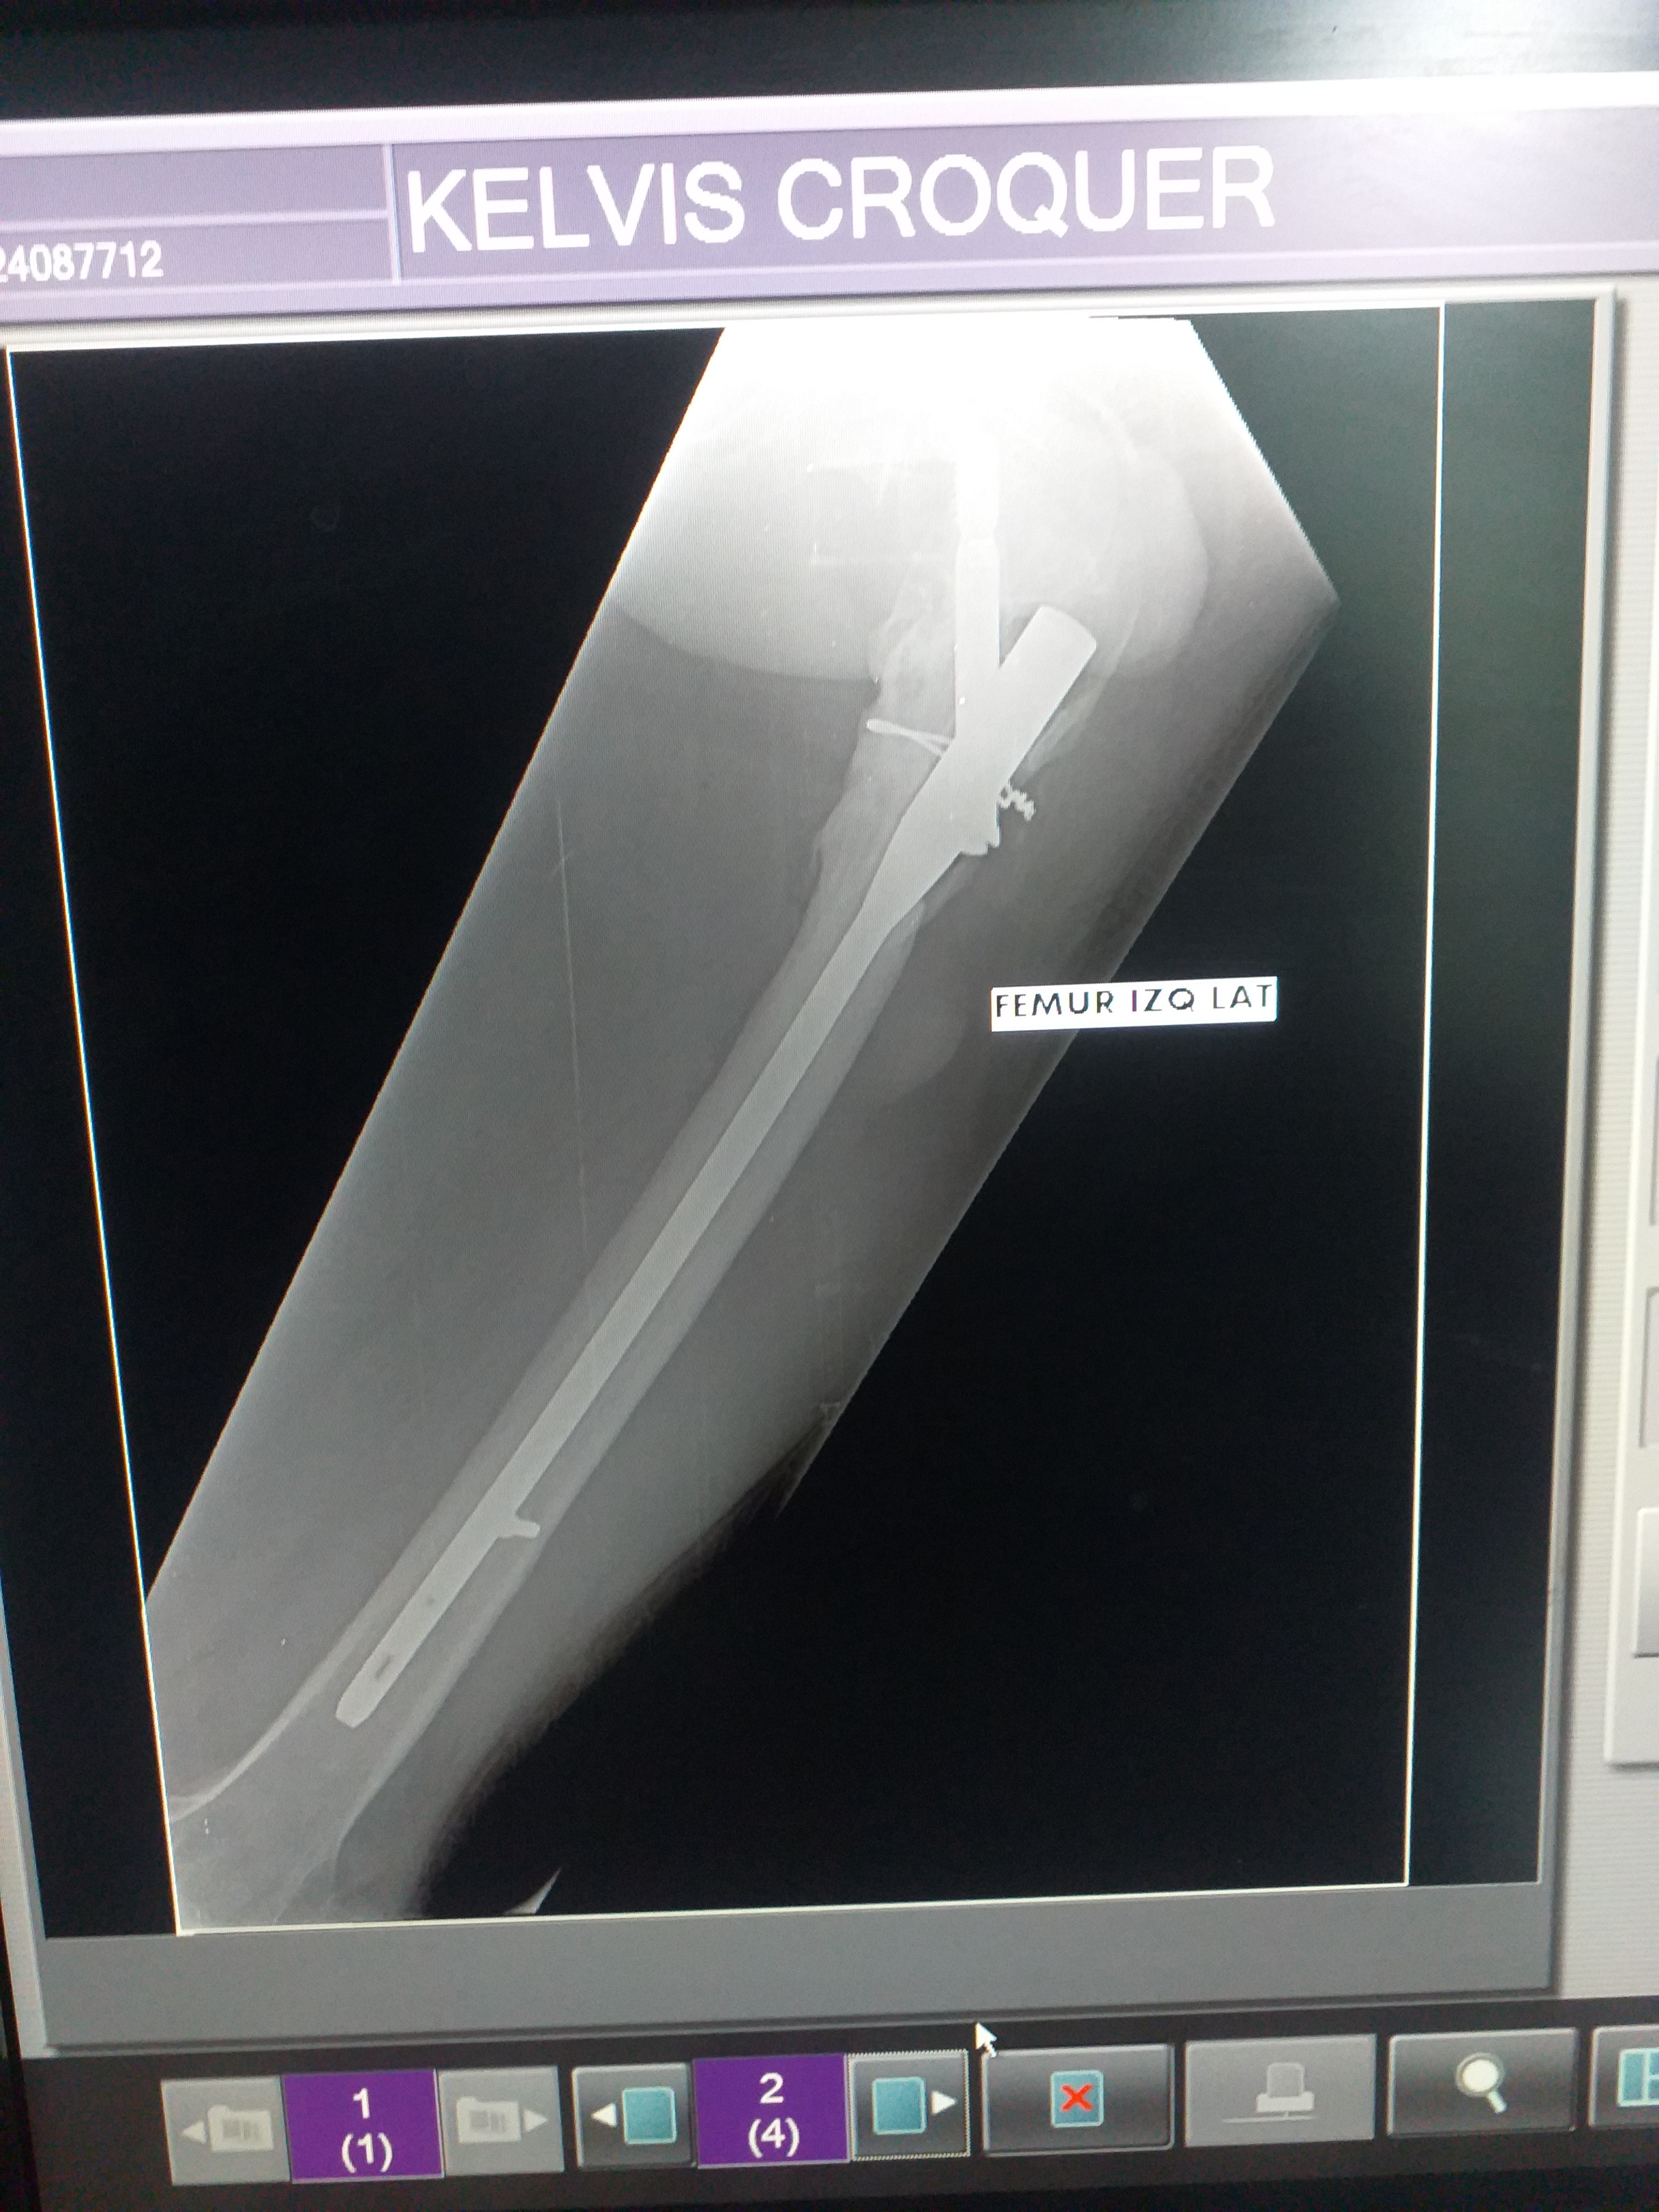

¡Hola! Me llamo Kelvin Cróquer y estoy recaudando fondos para una intervención quirúrgica de caracter de urgencia, debido que me tienen que realizar:

- Limpieza Quirúrgica

- Toma de muestra para cultivo

- Antibiograma

- Retiro de material de Osteosíntesis.

Porque tengo riesgo de que se agudice una Osteomielitis Crónica (infección de hueso).